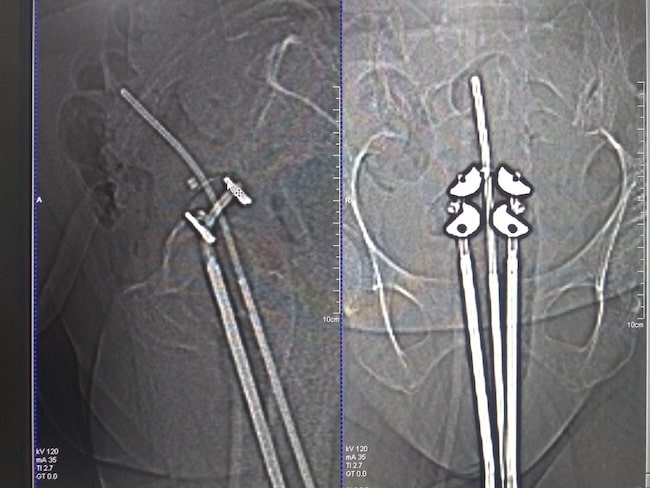

Terapi radiasi pada kanker endometrium risiko tinggi dapat berupa radiasi eksternal ataupun brakhiterapi. Brakhiterapi dapat berupa brakhiterapi intrakaviter ataupun brakhiterapi vagina.[1-4]

Dalam penelitian lain, dengan sampel yang lebih sedikit yaitu 10 pasien kanker endometrium inoperable dan mendapatkan pengobatan brakhiterapi, didapatkan bahwa kanker endometrium stadium I-II dapat dikontrol dengan baik secara lokal dengan toksisitas minimal melalui brakhiterapi HDR (high dose radiation).[4]